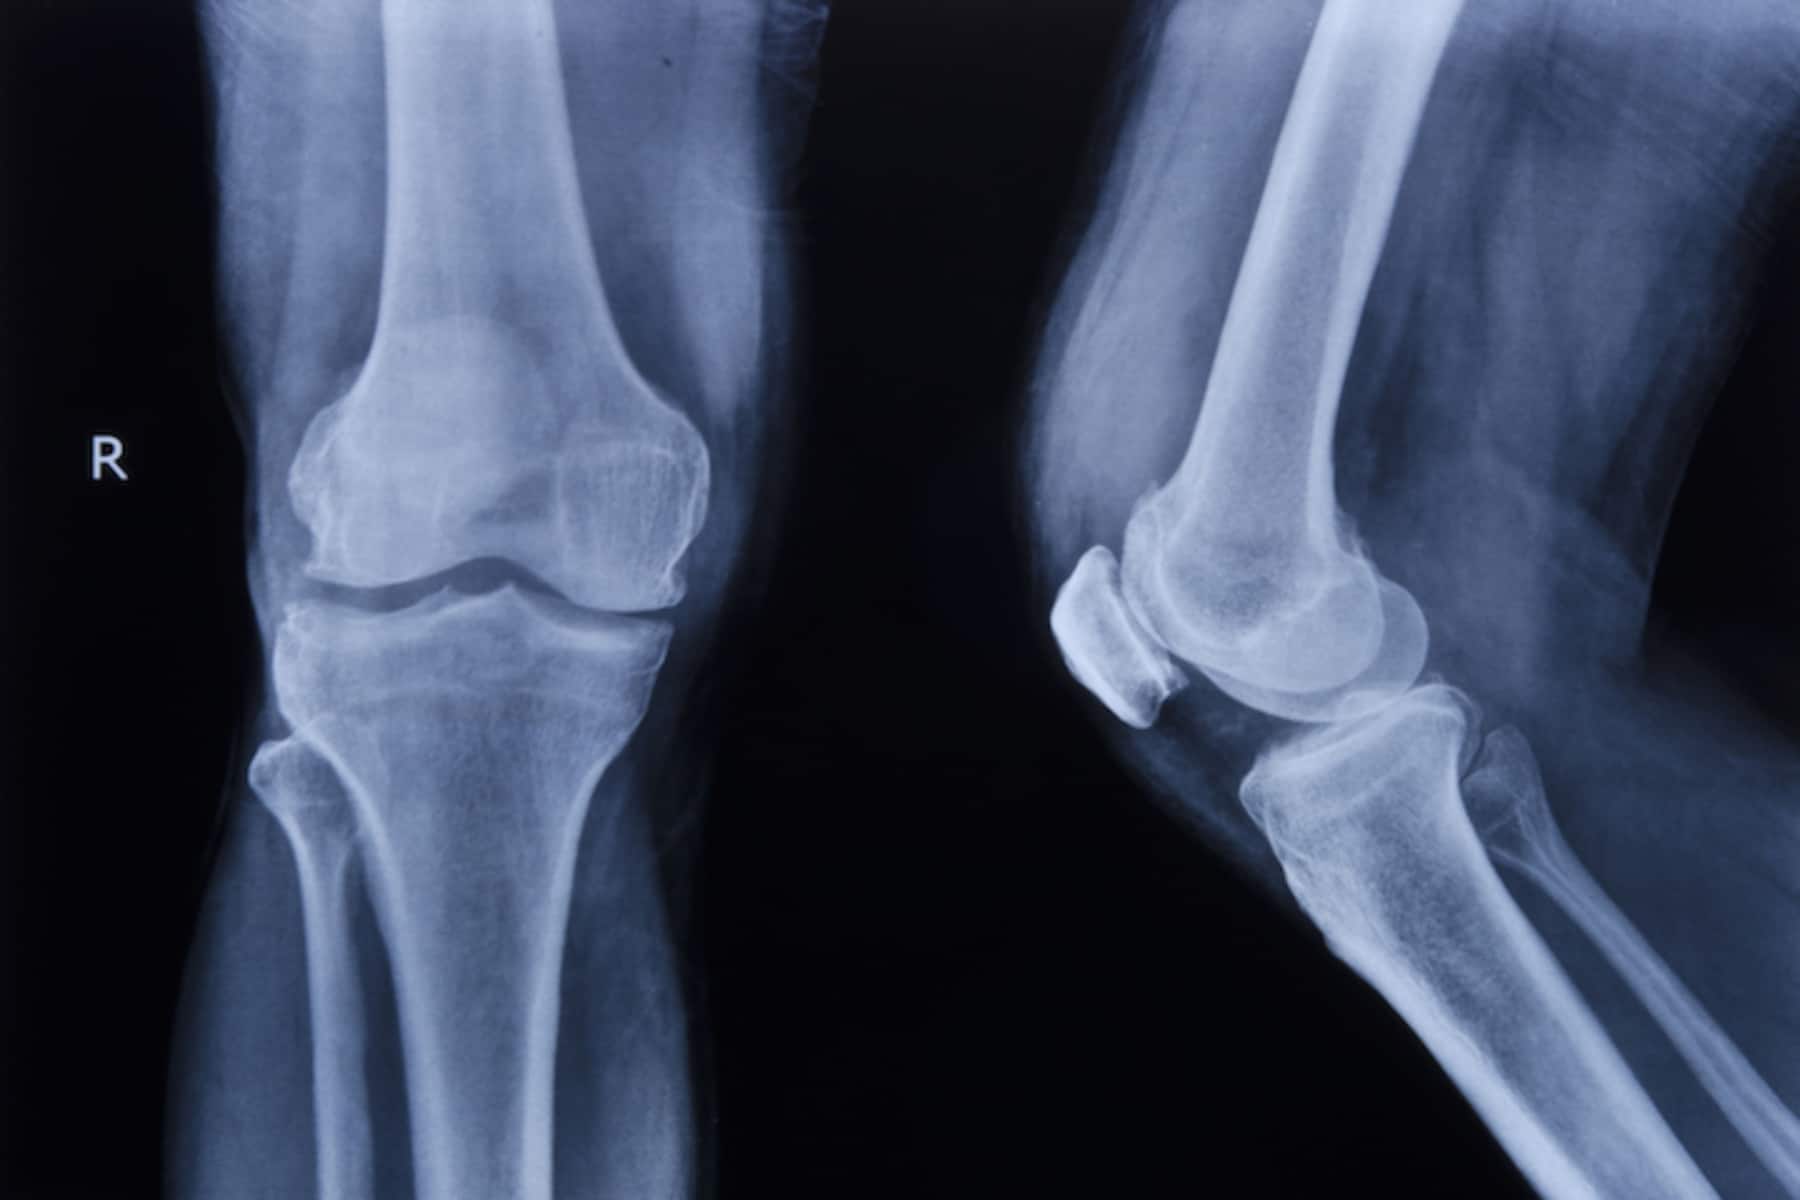

Η διάγνωση γίνεται συνήθως με κλινική εξέταση και απεικονιστικές μεθόδους, όπως ακτινογραφία ή πιο ευαίσθητες εξετάσεις όταν χρειάζεται. Στα αρχικά στάδια, το κάταγμα μπορεί να μην είναι εμφανές σε απλές ακτινογραφίες, γεγονός που δυσκολεύει την έγκαιρη ανίχνευση.